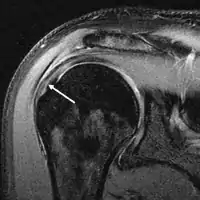

التصوير بالرنين المغناطيسي

التصوير بالرنين المغناطيسي والتصوير باستخدام الامواج فوق الصوتية [24] متماثلان في الفعالية ومفيدان في التشخيص، على الرغم من وجود ننائج إيجابية خاطئة في كليهما بنسبة [15-20%].[25] الرنين المغناطيسي يستطيع بكفاءة اكتشاف اغلب التمزقات الكلية، على الرغم من احتمالية تفويت الصغيرة منها (التي تكون بحجم رأس الدبوس)، في هذه الحالات يستخدم الرنين المغناطيسي مع حقن مادة التباين، الرنين المغناطيسي للمفصل ربما يساعد لتأكيد التشخيص. يجب أن يؤخذ بعين الاعتبار أن الحصول على صورة رنين مغناطيسي طبيعية لا يستثني تماماً التمزقات الصغيرة (نتائج سلبية خاطئة)، بينما لا يستطيع اكتشاف وجود تمزق جزئي كذلك.[26] لكنها تعد حساسة في اكتشاف تآكل الأوتار (أمراض الأوتار) لكن لا تميز بين الوتر المتآكل والوتر الممزق جزئياً. مجدداً الرنين المغناطيسي للمفصل يساعد في التمييز بين الاعتلالات المختلفة [26] بحيث تصل دقته إلى 91% (9% نسبة الخطأ) والتي تعني أن الرنين المغناطيسي للمفصل يعد موثوقاً في اكتشاف التمزقات الجزئية في الكفة المدورة، [26] إلا أنه لا ينصح باستخدامه بشكل روتيني عادةً لأنه يتطلب إدخال حقنة في المفصل مما يزيد من خطورة التعرض للعدوى، وبناءً عليه فإن هذا الفحص يترك للحالات التي يكون فيها التشخيص غير واضح.